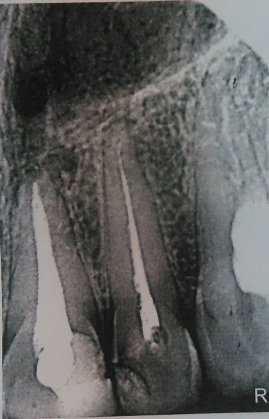

Здравствуйте! Есть ли у меня киста? Если да, то как срочно нужно делать операцию и как она называется?

Какой зуб вы имеете ввиду? Уточните. 18 и 48 зуб необходимо удалить. Далее расскажу после уточнения.